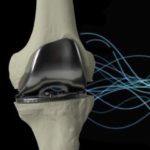

Η ολική αρθροπλαστική του γόνατος είναι μια επέμβαση αντικατάστασης των αρθριτικών επιφανειών του γόνατος με ειδικές προθέσεις, η οποία έχει ως σκοπό να απαλλάξει τον ασθενή από τον πόνο και την αναπηρία της αρθρίτιδας, επιτρέποντάς του να ανακτήσει τη λειτουργικότητα της άρθρωσης και να βελτιώσει την ποιότητα της ζωής του.

Η σωστή τοποθέτηση των εμφυτευμάτων της ολικής αρθροπλαστικής επηρεάζει τη λειτουργία της καθώς και την επιβίωση της στο χρόνο. Επίσης μελέτες έχουν αναδείξει το σημαντικό ρόλο της σωστής εξατομικευμένης τοποθέτησης των προθέσεων του γόνατος με την μετεγχειρητική ικανοποίηση του ασθενούς.

Με βάση αυτή την ανακατασκευή ο χειρουργός ορθοπεδικός έχει τη δυνατότητα να εκτελέσει εικονικά το χειρουργείο στον ηλεκτρονικό υπολογιστή, επιλέγοντας το μέγεθος των προθέσεων καθώς και τον βέλτιστο προσανατολισμό τους, στους τρεις άξονες κίνησης του γόνατος (μετωπιαίο, εγκάρσιο και οβελιαίο ), έχοντας ως γνώμονα την επιθυμητή διόρθωση του μηχανικού άξονα εξατομικεύοντας το χειρουργείο στις ανάγκες του κάθε ασθενή.

Αυτό έχει ως αποτέλεσμα την πιστή ευθυγράμμιση των προθέσεων βάση του εξατομικευμένου προεγχειρητικού πλάνου μελέτης.

Έτσι η ολική αρθροπλαστική εφαρμόζεται με εξατομικευμένο και προβλέψιμο για κάθε ασθενή τρόπο, λαμβάνοντας υπόψη τις μοναδικές ανατομικές ιδιαιτερότητές του.